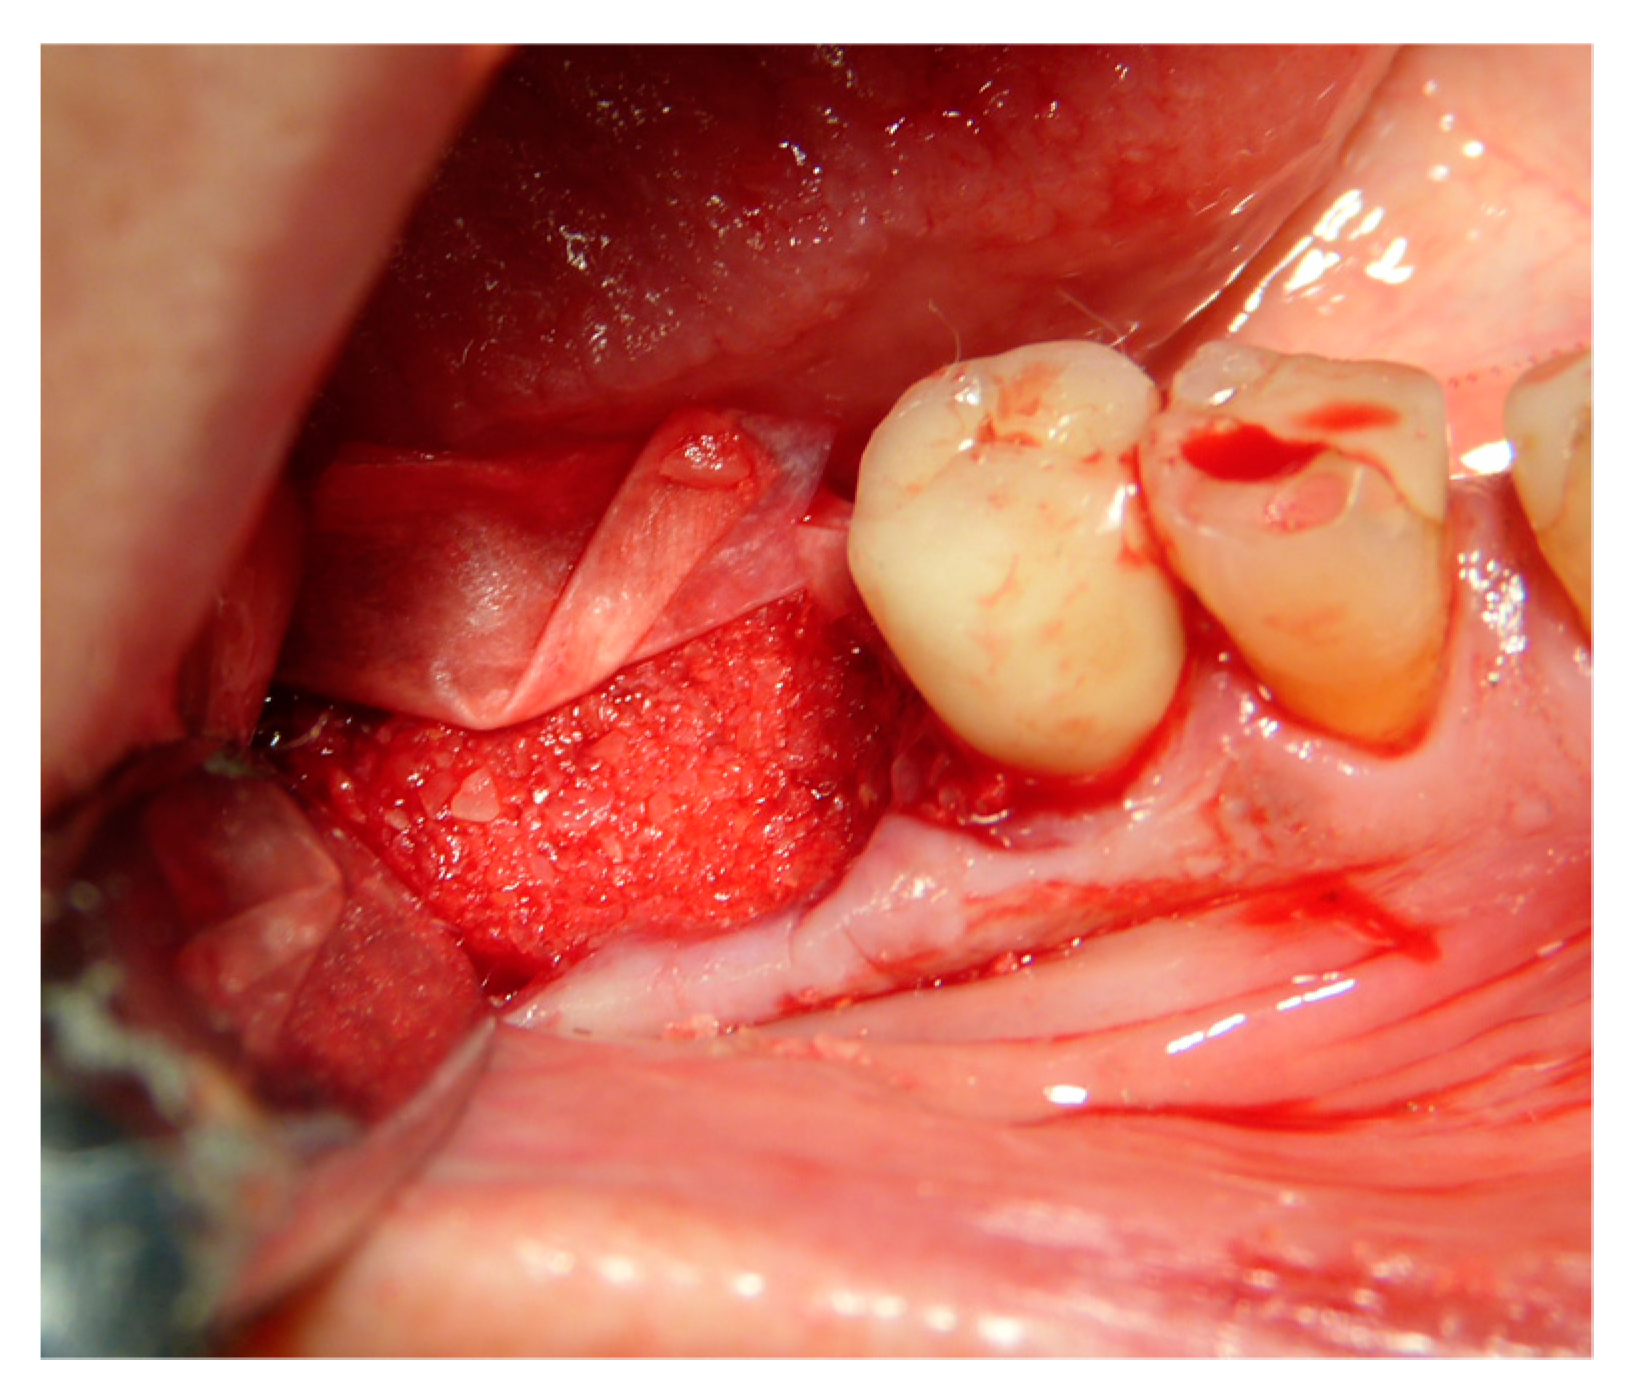

2.5. Surgical Procedures and Follow-Up